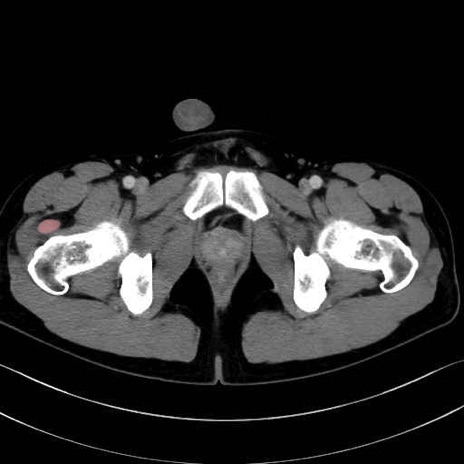

外側広筋(vastus lateralis) のCT画像の解剖

外側広筋 (Vastus lateralis)